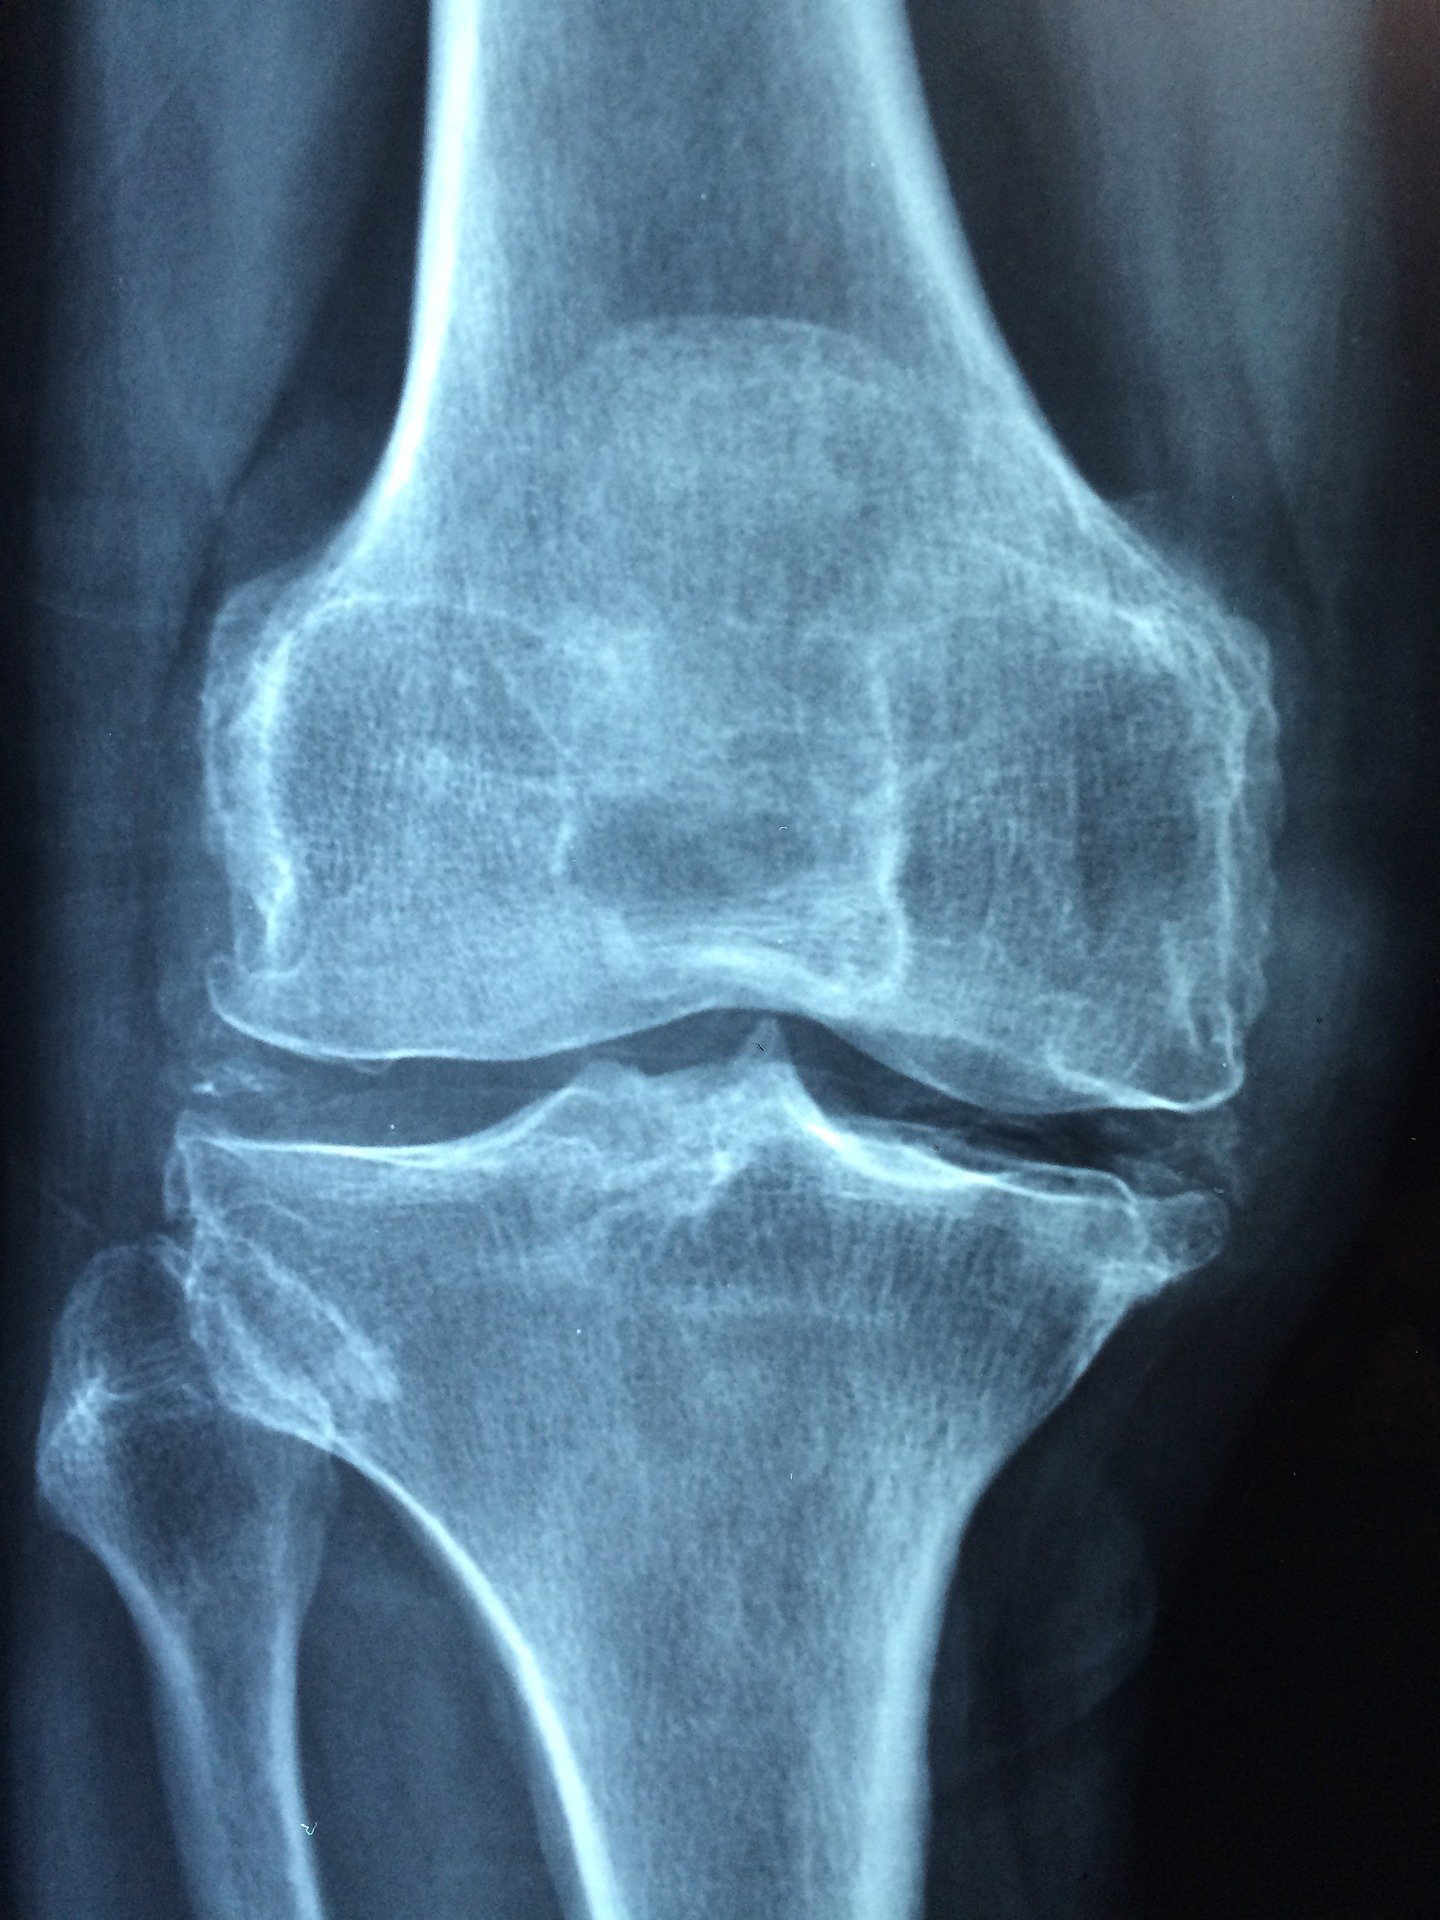

C'est le type de rhumatisme qui se produit fréquemment chez les humains. En général, celui-ci ne pose pas de problèmes graves. Il affecte principalement les genoux, la colonne vertébrale, les épaules, les hanches et les mains. Le rhumatisme dégénératif est une affection qui endommage rapidement le cartilage articulaire. Ce dernier est susceptible de disparaître complètement lorsque la maladie aura atteint un stade avancé.

Lorsque les articulations sont très sollicitées pendant une longue période, le cartilage s'irrite, s'affaiblit, se rompt et ne se régénère pas suffisamment. Et tout cela finit par provoquer une inflammation des articulations. Dans sa première apparition, l'arthrose se manifeste sur les grandes articulations, fortement stressées.

Le patient remarquera une raideur ou un gonflement accompagné de douleur au niveau de ces dernières.